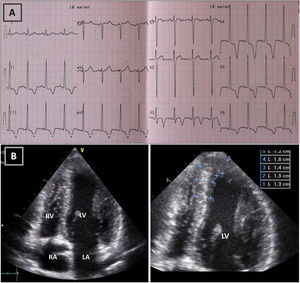

Resting electrocardiogram (ECG) (top) and transthoracic echocardiogram (TTE) (bottom), before detraining. (A) ECG with voltage criteria for LV hypertrophy and marked deep T-wave inversion in leads I, II, III, aVF and V3-V6, with ST-segment depression; (B) TTE (apical 4-chamber view), showing moderate asymmetric hypertrophy, localized at the mid-apical segments of the left ventricle, with maximum wall thickness of 16 mm. LA: left atrium; LV: left ventricle; RA: right atrium; RV: right ventricle.